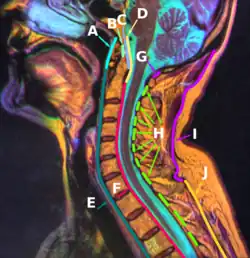

E:Anterior longitudinal ligament

Median sagittal section through the occipital bone and first three cervical vertebræ.